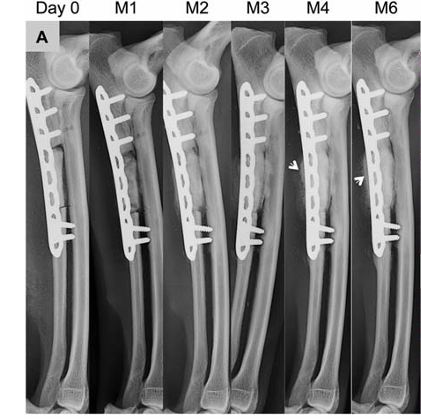

犬尺骨缺损骨修复监测

数据来源:DOI:10.1002/jbm.a.36384